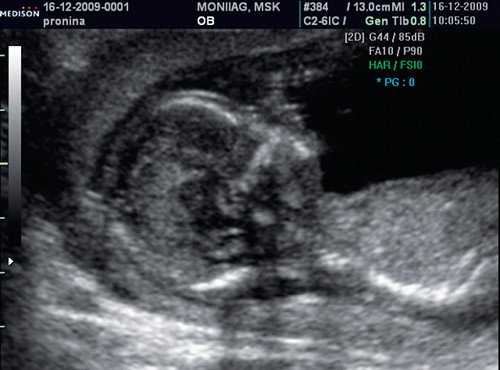

Копчико-теменной размер плода (КТР) для проведения скрининга I триместра должен быть в пределах 45-84 мм. Для оценки носовой кости в I триместре беременности необходимо соблюдать строгие условия. Это адекватное увеличение (на снимке должны быть только голова и верхняя часть грудной клетки), среднесагиттальный скан (должны быть визуализированы эхогенный кончик носа, небный отросток верхней челюсти, диэнцефалон), нос представлен тремя "К" (кончик носа, кожа, кость). Кожные покровы и кости носа визуализируются в виде знака "равенства", нос параллелен датчику.

Такие правила, как размер плода, адекватное увеличение, среднесагиттальный скан идентичны таковым при измерении ТВП. Таким образом, при выведении корректного скана для измерения ТВП, что является обязательным при проведении УЗ-исследования в сроки 11-14 нед беременности, оценка носовой кости проводится в том же самом срезе, не требуя получения дополнительных изображений.

Если все критерии соблюдены, то на уровне носа плода должны быть видны три четко различимые линии: верхняя линия представляет собой кожу, книзу от нее визуализируется более толстая и более эхогенная, чем кожа носовая кость. Третья линия, визуализируемая кпереди от носовой кости и на более высоком уровне, чем кожа - это кончик носа (рис. 1).

Рис. 1. Нормальная носовая кость.